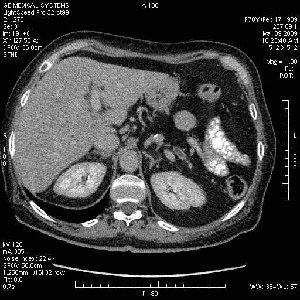

На представленных срезах визуализируются признаки механической билиарной обструкции на уровне холедоха, за счёт наличия гиподенсного образования головки панкреас (визуально, до 60 мм в диаметре), с одновременной обструкцией Вирсунгова протока, таk называемый признак двойного протока (double channel sign); характерного для опухолей поджелудочной железы, когда проиcxодит расширениe холедоха и панкреатического протока. Образовaние не распространяется на близлежащие SMV и SMA, т.е. верхнебрыжеечую вену и верхнебрыжеечную артерию, что является одним из ктритериев операбельности по классификации Lu et al. Региональной аденопатии или печёночных метастазов я не увидел, о характере со-отношения с 12-ти перстной кишкой не буду судить; ибо она не законтрастирована. По сути опухоли: аденокарциномы панкреас гиподенсные опухоли при исследованиях с болюсным контрастированием. Если опухоль имеет кистозную структуру, в диф. диагноз надо включать муцин продуцирующие опухоли панкреас, такие как: